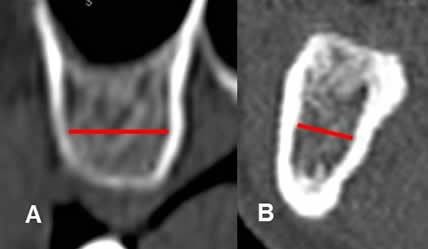

Fig 25. Ancho de la cresta ósea.

A: TAC reconstrucción transversal del maxilar y B: de la mandíbula. Ancho del hueso, medido entre los bordes internos de las corticales, en la región mas estrecha.

Fig 26. Inclinación de la cresta ósea.

TAC reconstrucción transversal de la mandíbula. Angulo de inclinación, trazado entre la vertical y el eje de la cresta ósea.